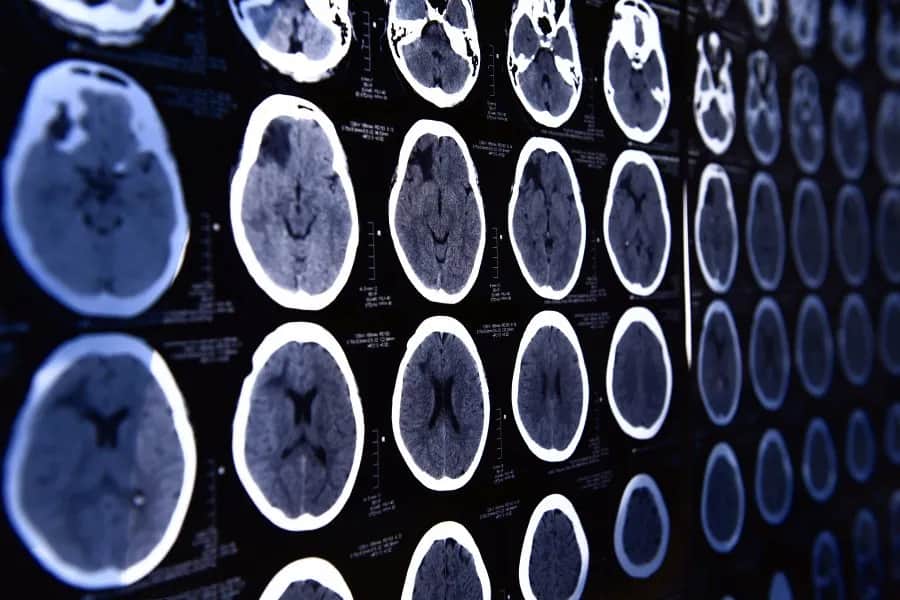

Dowiedz się, co wykrywa tomografia głowy. Poznaj jej zastosowania w diagnostyce urazów, nowotworów i procesów zapalnych, które mogą uratować twoje zdrowie.